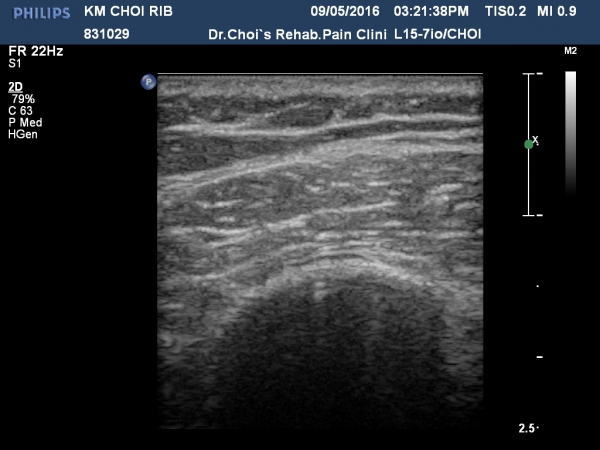

3ÁÖ ÈÄ ÃßÀû°Ë»ç¿¡¼­ °¡°ñ(callus)Çü¼ºÀÌ °üÂûµÈ´Ù(»çÁø 5, 6, 7, 8).